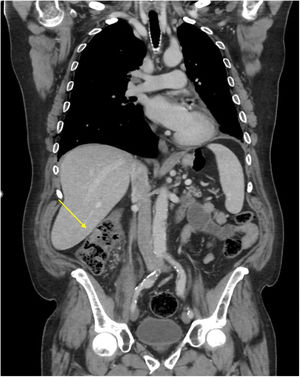

En una tomografía computarizada de control realizada 10meses después del diagnóstico se objetivó un engrosamiento mural del colon ascendente (fig. 1). Se realizó una colonoscopia, observándose en colon derecho una úlcera superficial de aspecto inespecífico (fig. 2). La histopatología fue compatible con metástasis colónica de carcinoma escamoso pulmonar (fig. 3).